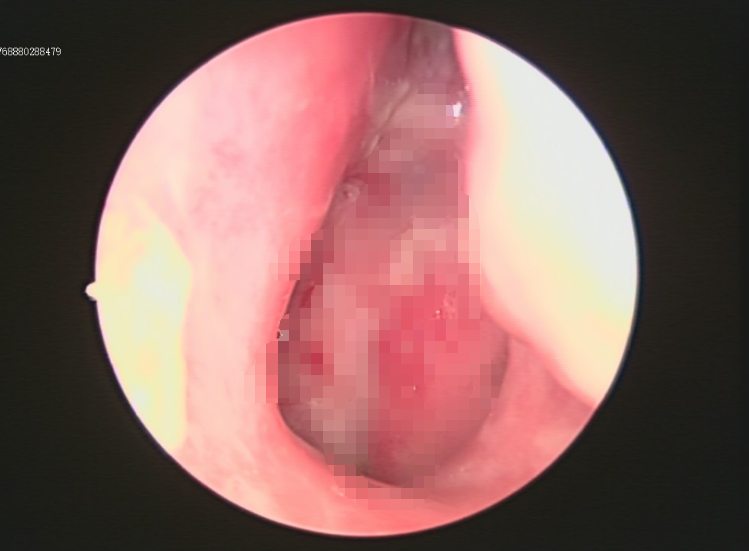

为进一步明确病理性质,门诊行电子鼻咽镜检查并尝试活检,但因病灶位置深在、解剖结构复杂、常规路径难以抵达核心区域,未能取得阳性结果。

术中依托超声支气管镜实时成像系统,动态显示病灶位置及周围血管结构,实现穿刺路径可视化。

在精准导航下,穿刺针准确进入MRI所示可疑结节区域,同时有效避开重要血管和神经结构,大幅提升操作安全性与取材成功率。

耳鼻咽喉科团队精准把握鼻咽——颅底的复杂解剖结构,呼吸内镜介入专家熟练操控超声支气管镜完成精准穿刺,两学科优势互补,突破单一专科技术边界,充分体现了我院多学科协作模式在疑难复杂病例中的强大实力。